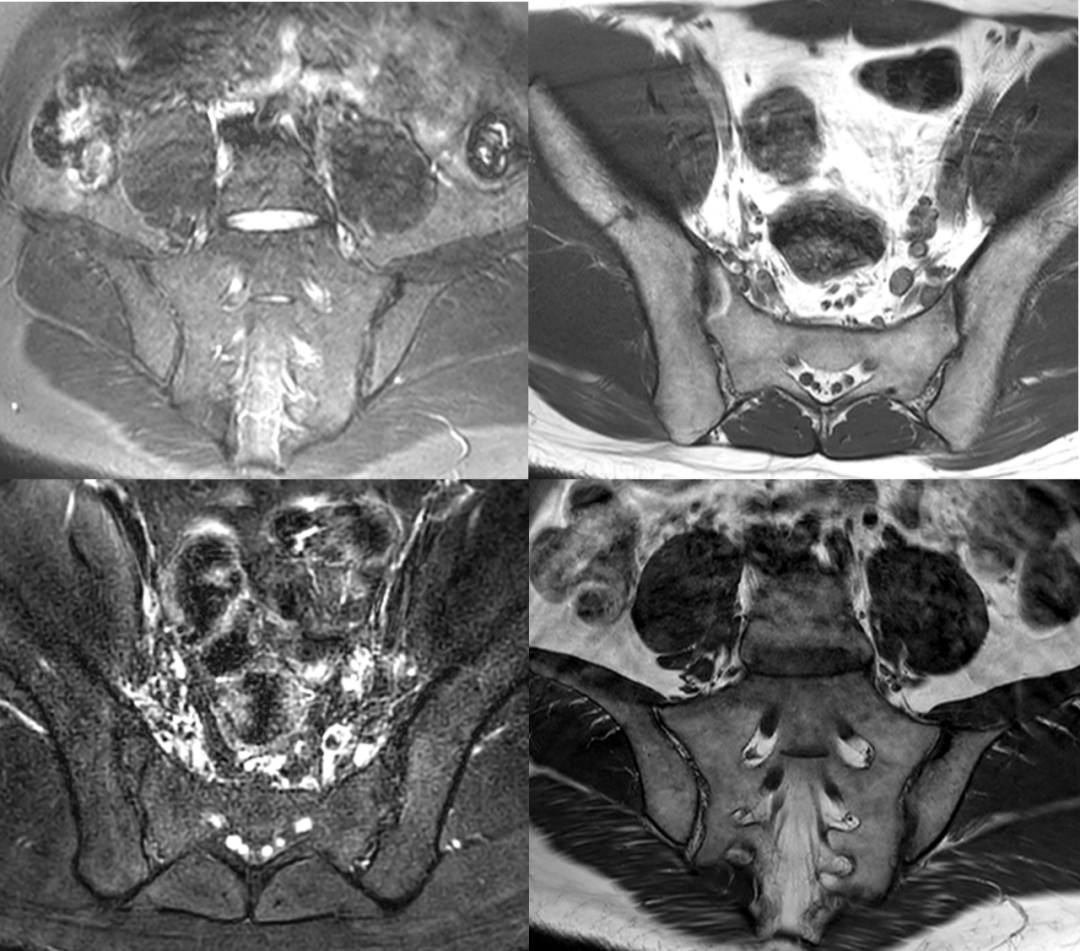

HLA-B27基因檢測可以幫助確定您患強直性脊柱炎的總體風(fēng)險,但醫生可能還會(huì )進(jìn)行其他檢測來(lái)幫助診斷這種疾病。這些檢查包括:

• 影像學(xué)檢查,如X光或核磁共振成像